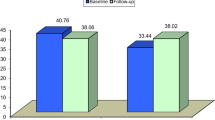

The CMR examinations were performed 3 ± 2 days and 90 ± 8 days after primary PCI. The LVEF at baseline was 57.5 ± 9.4%, which significantly improved to 62.0 ± 9.6% at 90 days (p < 0.001). The total infarct mass at baseline was 33.5 g (21.8; 41.9) which decreased to 23.1 g (14.6; 30.2) at 90 days. The analysis of CMR derived MVO assessment were performed on the first CMR scan performed at 3 ± 2 days. The stress infarct region MBF was higher than the resting infarct region MBF [24.3 ± 10.1 vs 14.8 ± 5.1 ml min−1 g−1 (mmHg bpm/104)−1, p < 0.001]. Stress infarct region MBF correlated with the extent of early MVO (r = −0.748) and late MVO (r = −0.682). The resting infarct region MBF also correlated with the extent of early MVO (r = −0.524) and late MVO (r = −0.46). Infarct region MBF difference correlated with the extent of late MVO (r = −0.474) and early MVO (r = −0.528). Late MVO was present in 31 patients (78%) while early MVO was present in 29 patients (73%). There were 2 patients (5%) who had late MVO without early MVO. The presence of late (60 vs. 70%, p = 0.005) and early MVO (59 vs. 69%, p = 0.001) predicted LVEF at 90 days respectively. The presence of late (p = 0.015) and early MVO (p = 0.04) correlated with impaired TMPG. However MBG did not correlate with the presence of late (p = 0.886) or early (p = 0.688) MVO.

The extent of late MVO correlated best with LVEF at 90 days compared to the extent of early MVO, stress infarct region MBF, infarct region MBF difference and resting infarct region MBF (r = −0.754, r = −0.595, r = 0.595, r = 0.431 and r = 0.345 respectively). Infarct mass at baseline also correlated with LVEF at 90 days (r = −0.384). Maximal LGE score correlated with ejection fraction at day 90 (r = −0.431, p = 0.006) When evaluating angiographic parameters of MVO, TMPG (p = 0.002) but not MBG (p = 0.115) correlated with LVEF at 90 days. On univariate linear regression, extent of late MVO (β = −0.68) and stress infarct region MBF (β = 0.492) were better predictors of LVEF at 90 days compared to TMPG (β = −0.486). On multiple linear regression, extent of late MVO was the strongest predictor of LVEF at 90 days (p = 0.016), independent of infarct mass and other assessments of microvascular injury (Table 2). On post hoc analysis utilising likelihood ratio test, the addition of ‘Stress infarct region MBF’ to late MVO significantly improved the prediction of LVEF at 90 days (Chi-square (1) = 6.20, p = 0.013).